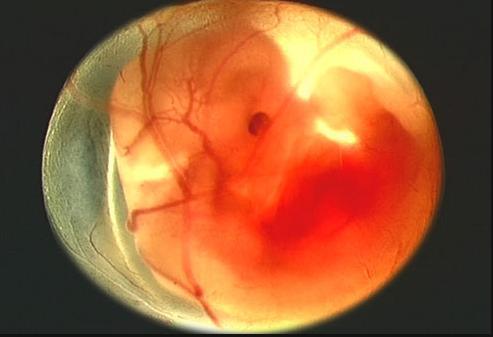

从怀孕一个月到怀孕十月每个月胎儿的发育图都在这里了真全

胎儿发育全过程图解 怀孕一个月胎儿图分析(全文)

五个半月的胎儿真实图

怀孕五个月胎儿图

怀孕5个月胎儿图

怀孕5个月胎儿图真实

孕五个月胎儿真实图片

五个月胎儿图片

五个月胎儿的样子

四个月真实胎儿图片